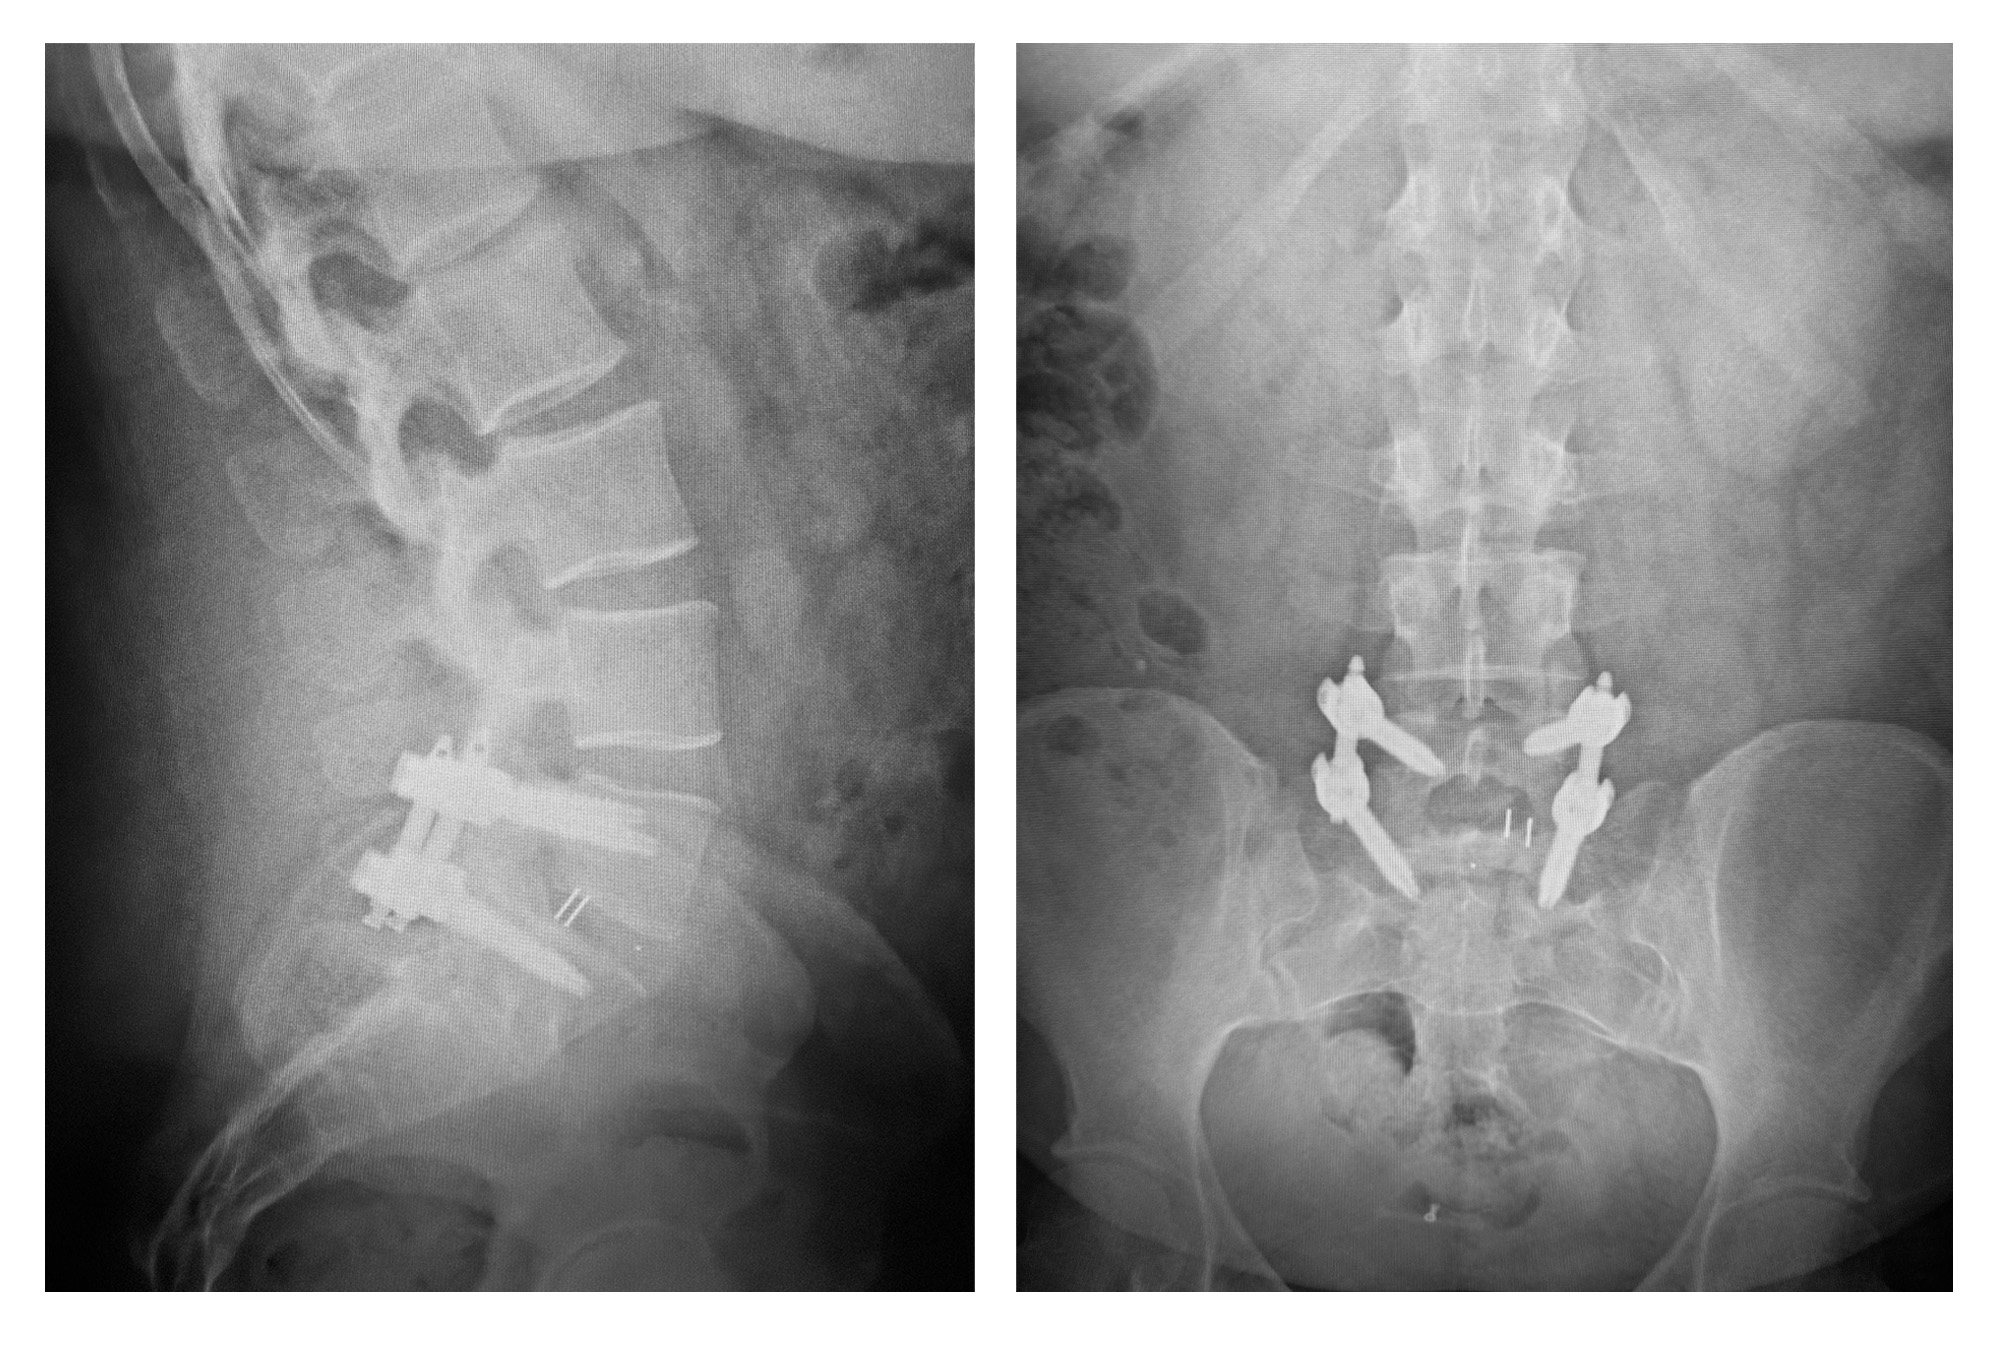

The Primus™ MIS Spinal Fixation System delivers versatility and efficiency through the power of adaptability in a compact, modular system. This minimally invasive modular screw system provides a vast array of implants engineered to work efficiently with intuitive instrumentation for a streamlined, consistent solution. The 5.5/6.0mm MIS system offers a multitude of multi-axial pedicle screws, self-tapping dual-lead cannulated, and diameters from 4.5mm to 8.5mm and lengths from 35mm to 55mm.